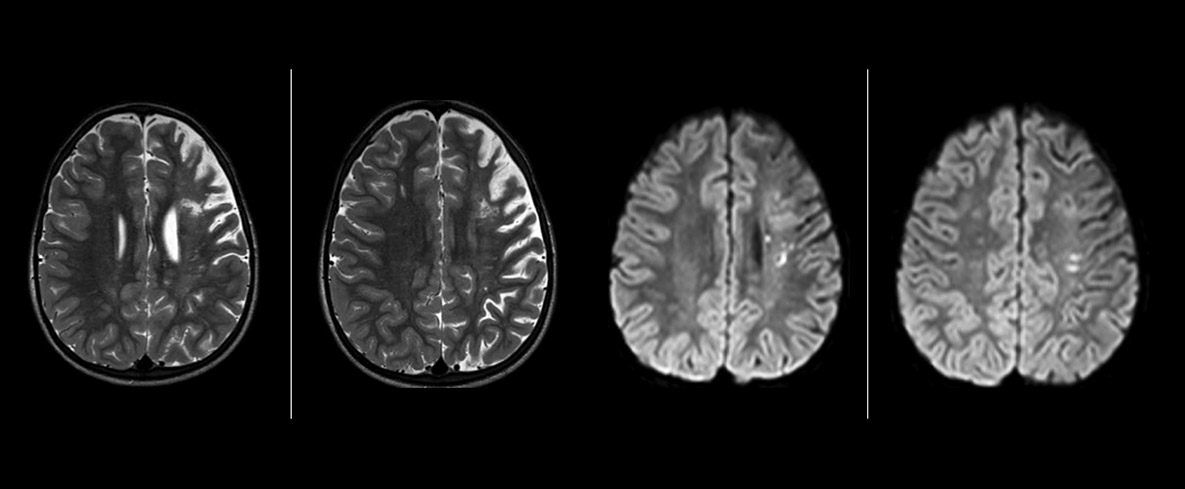

Pseudo-continuous Arterial Spin Labeling (pCASL, pseudo-kontinuierliche Spinmarkierung) wurde für die Bildgebung der zerebralen Perfusion ohne Kontrastmittel entwickelt. „Dies ist bei Kindern sehr erstrebenswert, da bei ihnen grundsätzlich versucht wird, die Gabe von Kontrastmittel weitestgehend einzuschränken“, erläutert Dr. Miller. Zunehmende Sicherheit bei spezifischen Anwendungen „Die Zuverlässigkeit von pCASL sicherten wir über einen Vergleich mit kontrastmittelbasierter Bildgebung ab. Nachdem wir uns davon überzeugt hatten, dass mit beiden Verfahren dasselbe dargestellt wurde, vergrößerten wir unsere Diagnosesicherheit noch über eine serielle Bildgebung im akuten Stadium bzw. in den langfristigen Stadien bei einer Anzahl von Patienten mit arteriellen Veränderungen.

Dr. Miller verwendet pCASL bei allen Patienten mit chronischen und akuten zerebrovaskulären Befunden wie akutem Schlaganfall sowie Patienten mit Anzeichen einer akuten Entzündung im Gehirn und gelegentlich bei Patienten mit Tumoren für eine Perfusionsbewertung des Tumors.

„In Kombination mit diffusionsgewichteter Bildgebung kann dieses Verfahren zu einer detaillierteren Beurteilung des Grades der Perfusionsstörung bei Patienten mit akuter Ischämie beitragen. Wir haben eine Reihe von Patienten, die unter chronischer arterieller Insuffizienz aufgrund früherer arterieller Störungen oder erworbenen arteriellen Veränderungen wie Sichelzellenanämie oder Neurofibromatose leiden. Gelegentlich manifestiert sich ein Krankheitsfortschritt beim Kind zunächst in einer reduzierten zerebralen Perfusion, bevor Schlaganfallsymptome klinisch oder in der diffusionsgewichteten Bildgebung manifest werden. Wir nutzen pCASL zur Unterstützung bei der Abgrenzung von Perfusionsstörungen.“

Anderen neuen Benutzern würde ich ebenfalls empfehlen, mit der Befundung von pCASL-Bildern im Vergleich zu anderen Standardbildgebungsverfahren zu beginnen – T2 und FLAIR und DWI –, bis sie selbst Sicherheit bei der Auswertung dieser Bilder gewinnen.“ „Der Nutzen von pCASL wird insbesondere bei Patienten mit chronischer zerebrovaskulärer Stenose deutlich, wo das Klinikteam Aufschluss darüber benötigt, wie die kompensatorischen Mechanismen des Gehirns wirken, um dessen ordnungsgemäße Durchblutung sicherzustellen. Das Klinikteam bezieht diese Funktionsweise der kompensatorischen Mechanismen häufig in die Entscheidung ein, ob ein chirurgischer Eingriff durchgeführt oder andere Maßnahmen ergriffen werden.“ „Eine weitere spezielle Anwendung besteht in der Beurteilung der zerebrovaskulären Reaktivität mit einer Diamox Perfusionsuntersuchung, bei der wir zwei Sätze mit pCASL-Bildern subtrahieren.“

„pCASL ist mittlerweile zu unserem bevorzugten Untersuchungsverfahren für die Perfusionsbewertung geworden und hat die DSC-basierte Perfusionsbildgebung mit Kontrastmittel hier abgelöst. Bei Patienten, für die kein Kontrastmittel vorgesehen war, können wir pCASL für die Perfusionsbildgebung durchführen, ohne die Untersuchung stoppen zu müssen. Der Patient wird einfach herausgeschoben und ein Zugang gelegt. Auch die Nachbearbeitung, die bei Kontrastmitteln mit dynamischer Suszeptibilität nötig ist, entfällt. Außerdem ist es möglich, eine Perfusionsbildgebung beim selben Patienten während einer Untersuchungssitzung zu wiederholen, was in Fällen, wo sich der Patient bewegt bzw. in Situationen hilfreich ist, wo ein Scan vor der pharmakologischen Perfusionsbildgebung erfolgen muss.“